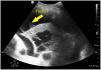

Paciente de 52 años con antecedente personal de síndrome de inmunodeficiencia adquirida, que ingresa en nuestra unidad por neumonía adquirida en la comunidad por Streptococcus pneumoniae. En la radiografía de tórax se objetiva infiltrado basal derecho y se realiza tomografía computarizada de tórax con hallazgos de neumonía necrotizante con probable absceso pulmonar incipiente. Presenta mala evolución, con hipoxemia refractaria a ciclos de prono, realizándose ecografía pulmonar. Se observa derrame pleural con trayectos fibrosos hiperecogénicos o signo del plancton en su interior (fig. 1, flecha 1), infiltrado basal derecho con hiperecogenicidad del parénquima por hepatización del mismo con broncograma aéreo, también interno (fig. 2, flecha 2), así como zonas trabeculadas hipoecogénicas bien delimitadas, compatible con neumonía necrotizante y absceso pulmonar (fig. 2, flecha 3).